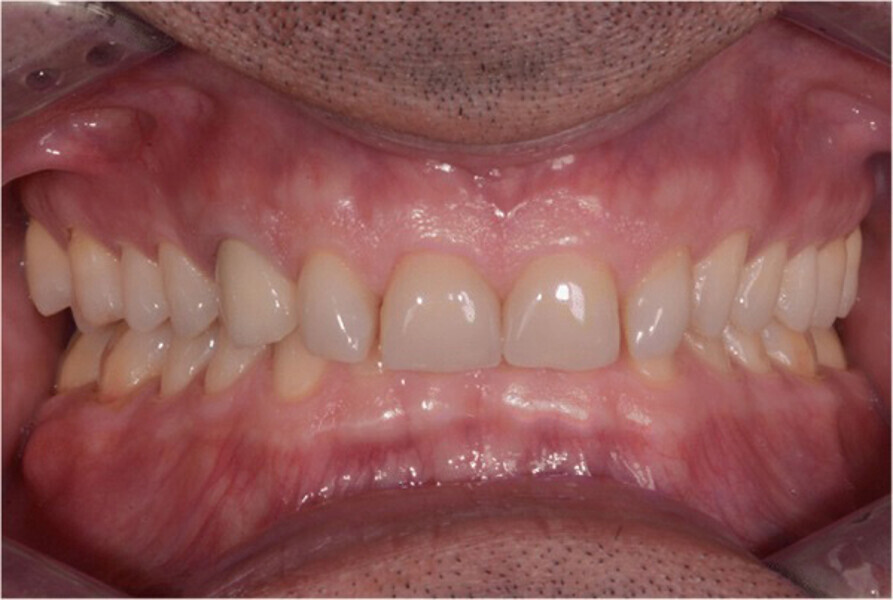

Fig. 14. Fotografías intraorales del tratamiento finalizado. a y b Vista frontal. c Vista oclusal de la mandíbula superior. d Vista oclusal de la mandíbula inferior.